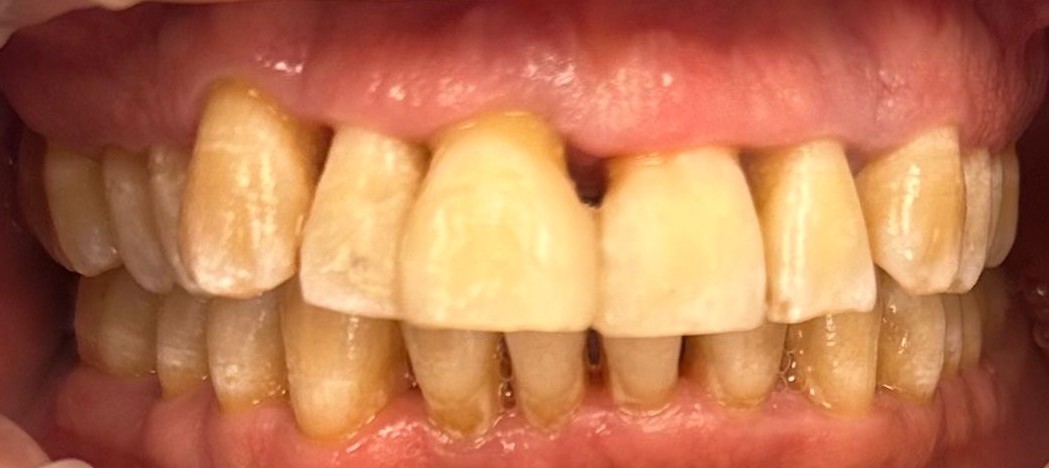

Este caso es muy típico en pacientes con enfermedad periodontal avanzada y sobrecarga funcional: comienzan notando una ligera movilidad en los dientes y, de repente, esa movilidad se vuelve generalizada, especialmente en los incisivos superiores. Ahí es cuando empiezan los problemas estéticos, la inseguridad al sonreír y la dificultad real para comer.

Este paciente acudió a mi consulta referido por otros pacientes, con un estado periodontal comprometido, una sobrecarga funcional muy marcada y una movilidad severa de los incisivos superiores. Era un paciente con gran fuerza masticatoria, un volumen óseo importante, pero con una calidad ósea deficiente.